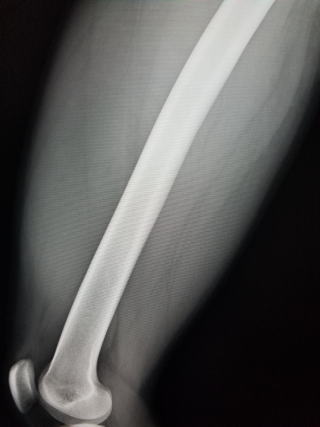

骨化性筋炎は、外傷や手術後などに局所で石灰化が起こり骨化する病気です。骨化が小さいものなら支障が無いこともありますが、大きくなると関節の可動域が障害され日常生活や運動で支障が出ることがあります。有名なのはコンタクトスポーツで相手の膝が太ももに入り、大腿四頭筋が損傷して血腫を形成し骨化するケースです。

文献や専門書には、骨化は成長して半年ぐらい大きくなる、骨粗鬆症で使うビスフォスフォネートでの保険外使用、ウロキナーゼにより血腫を溶かす治療などが書かれています。

自然経過が実際どうなるのか、はっきりと書いたものはありませんでした。今回の事例のように局所に負荷を掛けなければ、縮小してレントゲンで見えなくなり、また超音波でも著しく縮小することもあることが分かりました。おそらく、完全な骨化までには至らず、日常生活を普通に送る程度の局所安静の結果、生じた石灰化が吸収されたものと考えます。→海外の文献によると30%~40%ぐらいは吸収されて消失するとあります。

従って、受傷後の骨化が完成しないうちは、局所安静により早期であるほど吸収され消失する可能性があり得ることをわかりました。

早期リハビリの時代ですか、この病気だけは無理をしないことが重要となります。

受傷4週間目 レントゲンで大腿骨前面に石灰化を認めます。超音波では石灰化が成長してくっきりと見えています。 局所に負担を掛けない生活を継続してもらう。 |